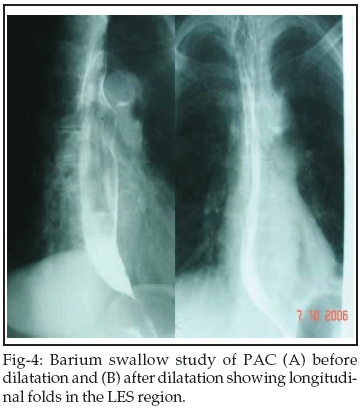

The balloon catheter needs to be held by the technician at the mouth guard to prevent its distal migration during air insufflation. We suggest "EASL" as a safer and an equally effective alternative to fluoroscopic assessment of dilatation of the LES. On looking at the LES from above, if the balloon walls run parallel and meet the stretched LES at right angles, the balloon "waist" is surely obliterated and the dilatation force is usually effective (Figure-2A): the dilatation of LES is likely to be inadequate if the balloon walls appear to converge at the LES (Figure-2B). "EASL" permits full distension of pneumatic balloon even without the use of a pressure guage. If parallel balloon walls continue to meet the stretched LES at right angles, further expansion may result in balloon rupture. Thus "EASL" can impart near-accurate information about effacement of the balloon "waist" and adequacy of LES dilatation. When combined with history of subjective improvement, "EASL" can surpass the need for serial LES manometry and radionuclide transit studies.23 However, we support the indication of an early post-operative contrast study to exclude oesophageal leak or perforation.24 Dilatation trauma to the LES results in muscle spasm in a zone with high resting pressures. Therefore, post-treatment flow of barium across the LES may not be apparent within 24 hours in spite of significant subjective relief.25 An early re-dilatation should be withheld in such cases. We encountered this situation in three (12%) patients. In our opinion, replacement of the classic "bird beak" deformity (Figure-3A) by a thin streak of barium (Figure-3B) or appearance of longitudinal folds within the LES region (Figure-4) indicate significant radiological improvement.